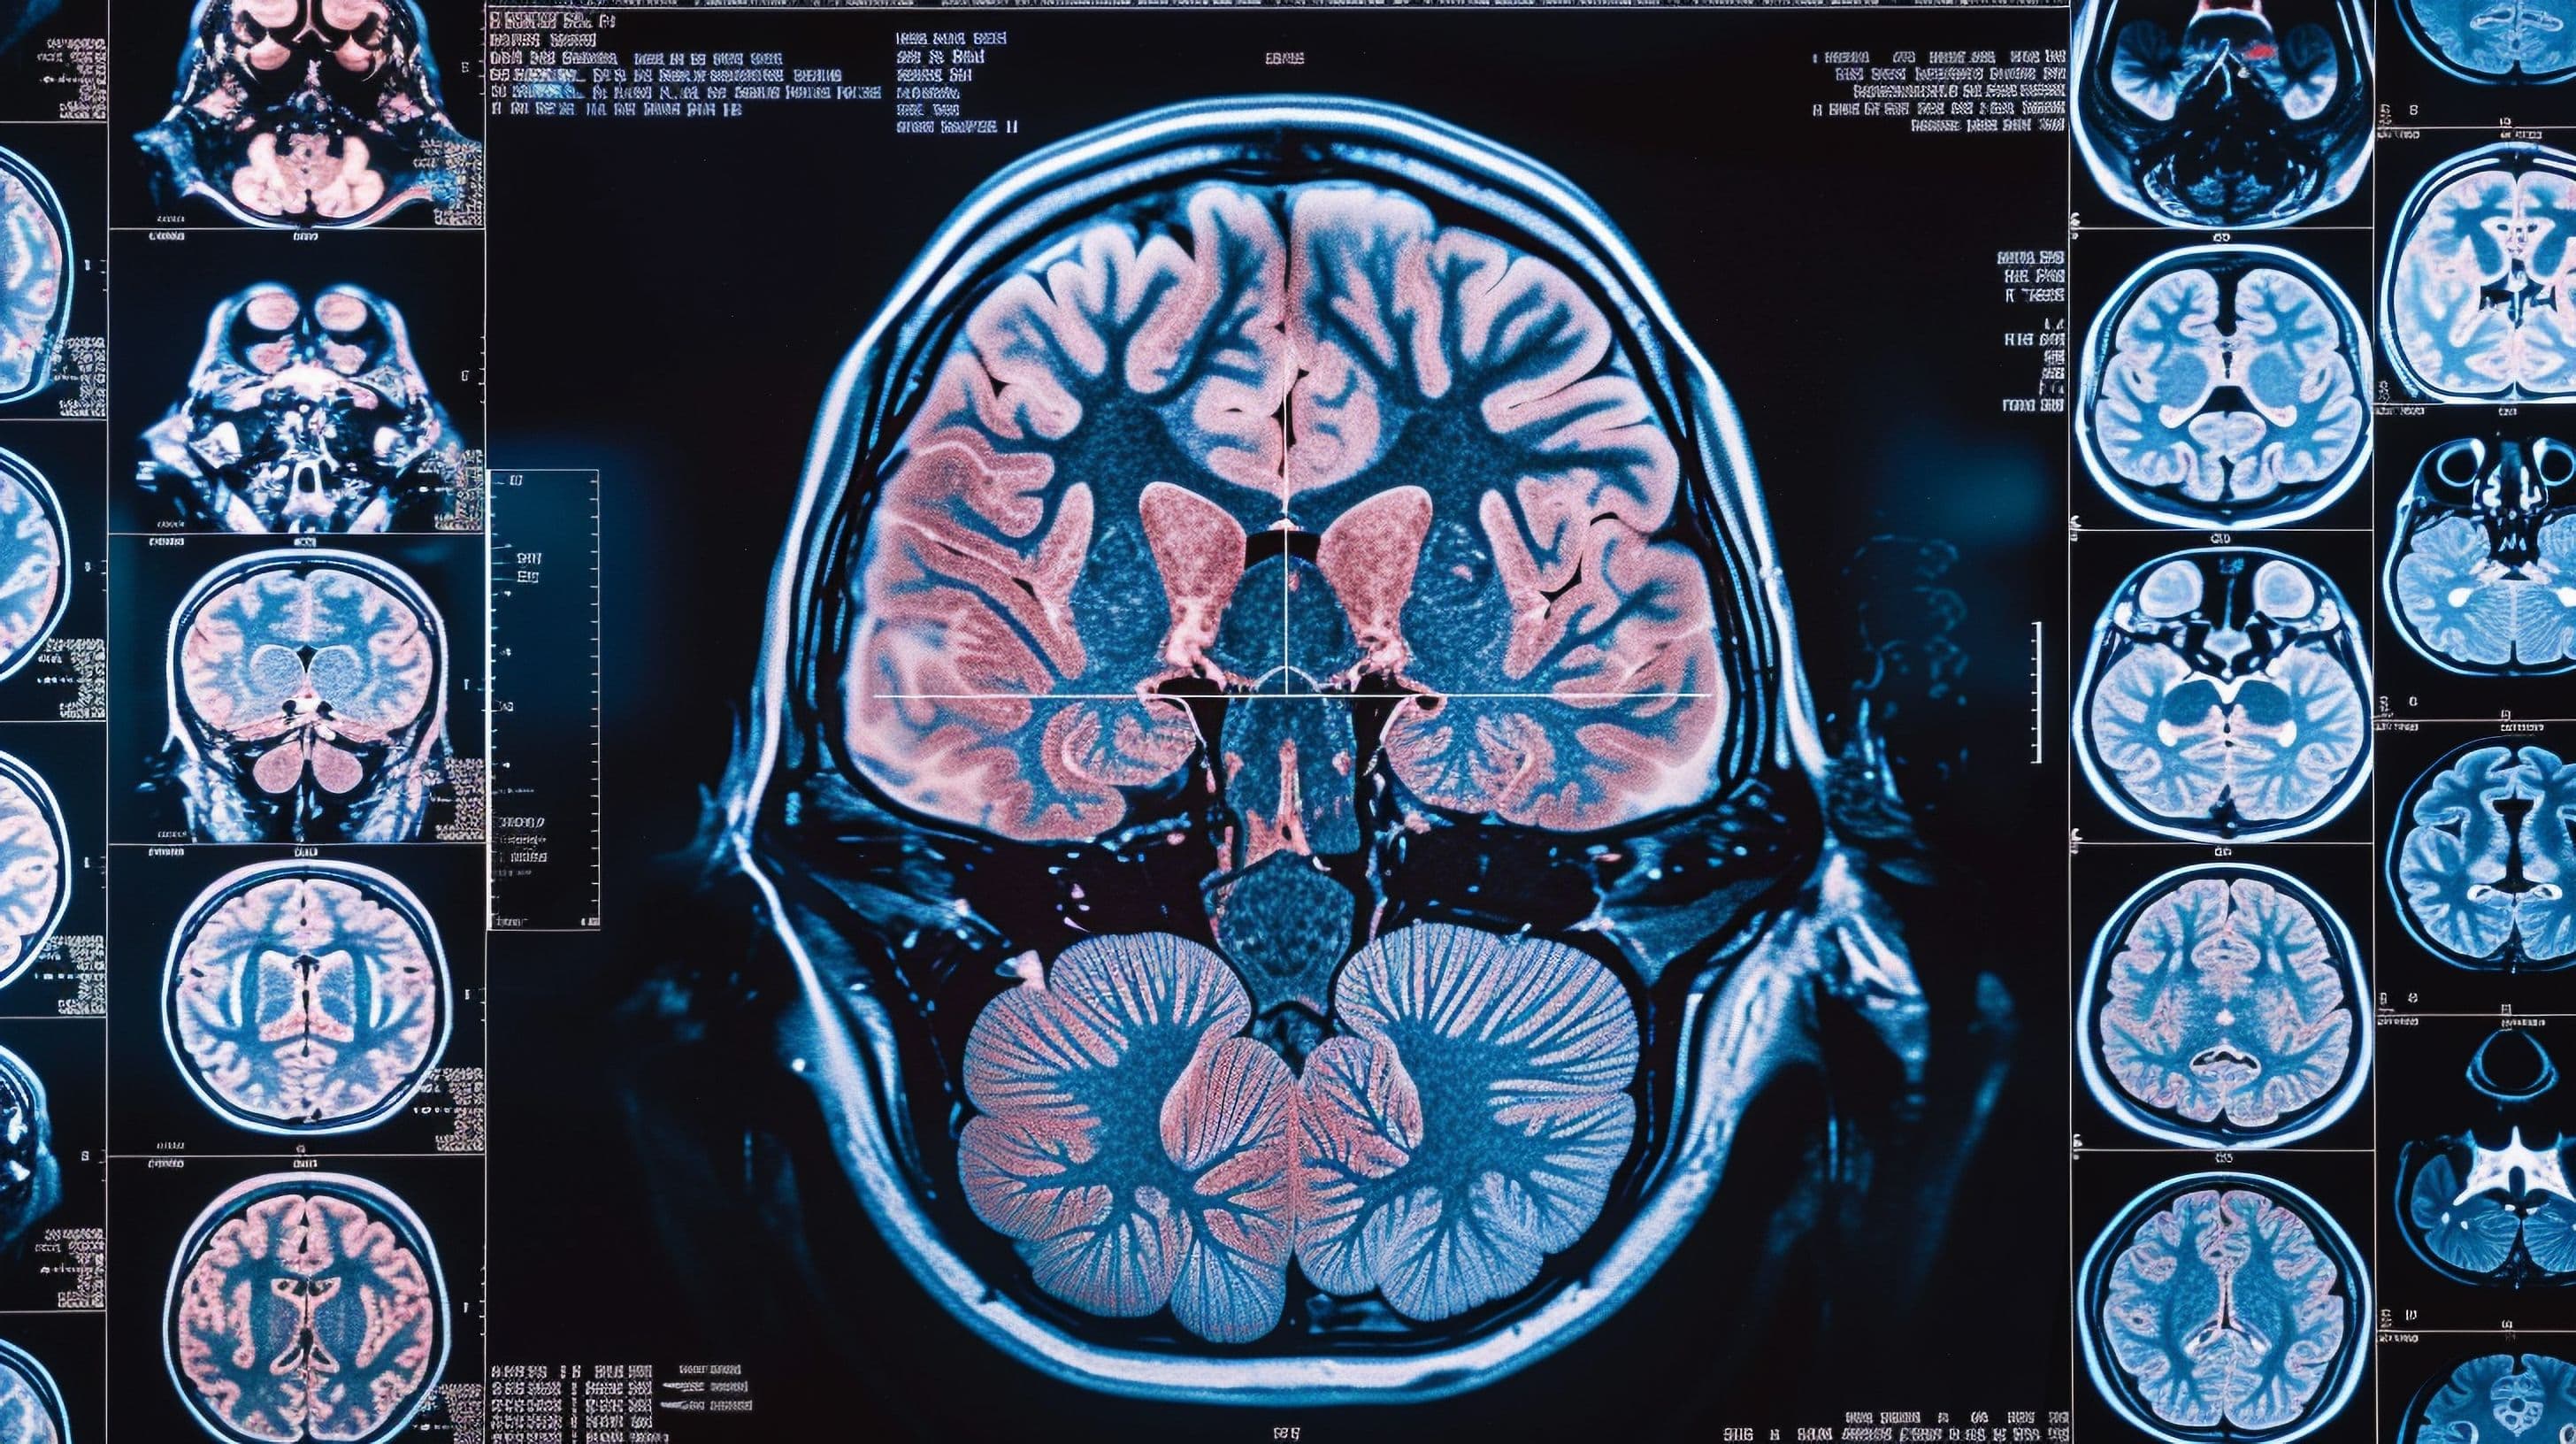

Brain injuries can have devastating consequences, but by identifying the exact location of these injuries, Brain Mapping Solutions empowers doctors and patients with the essential information for treatment.

Brain Mapping Solutions utilizes technologies like PRISM Imaging to detect injuries that are hard to identify, helping avoid misdiagnoses that could compromise patient treatment.

Location-Specific Injury Identification: Revolutionizing Brain Injury Diagnosis

This article highlights the importance of accurately identifying the location of brain injuries. It explains how Brain Mapping Solutions uses advanced imaging technology to pinpoint injury locations, helping medical professionals develop better treatment plans for their patients.